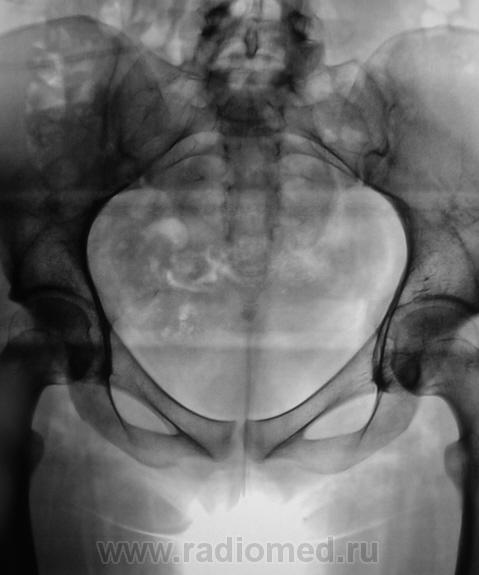

Из анамнеза известно, что примерно 2 месяца тому "летела" со сноутборга около 200 метров. Сейчас беспокоят боли в области спины, крестца и лонного сочленения. УЗИ было сделано всего, что только можно, везде - "норма". Хирурги, вроде-бы тоже ничего не находят. Но боли, видать значительные, походка вынужденная. На рентгенографию была направлена, как жест отчаяния, мол может быть, что-то найдут.

Так как "содержимое кишечника" не способствовало анализу изображений, пациентке было предложено, посетить кабинет повторно.

1. Не исключаю поперечный перелом S5.

2. Лонное сочленение очевидно,подверглось значительному растяжению (имеется локальный вакуум-феномен слева), умеренно выраженые явления симфизита (опять же - постравматического).

1. По первым снимкам не отпускало впечатление о повреждении левого крестцово-подвздошного сочленения. После подготовки вроде-бы все нормально, но все равно что-то гложет.

Возможно, перелом последнего копчикового тоже был?

Поздно заметил ветку.. увидел симфизит, перелом остистого L4, мазоль Co 5, и  конечно spina bifida S1 ))) глянуть бы межпозвоночные..